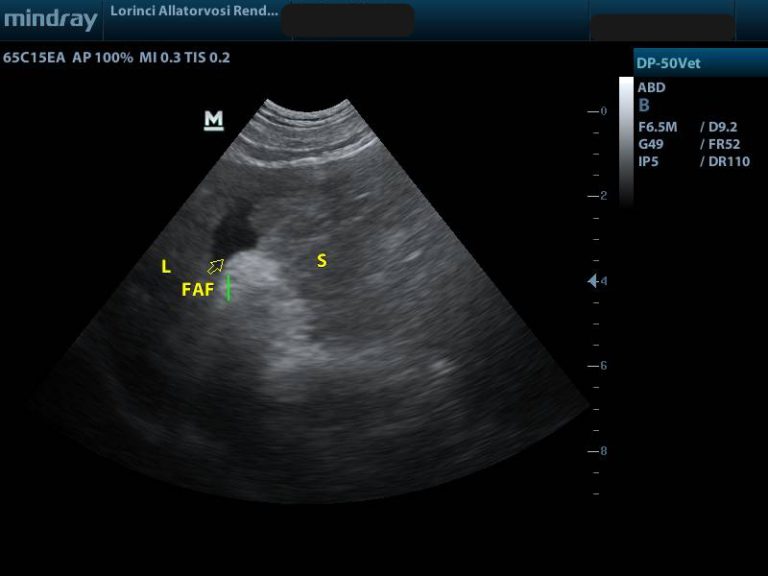

Megnagyobbodott lép hasi ultrahang felvétele

Megrepedt lépdaganat, következményes hasi folyadékgyülem

(képeken lévő rövidítések S: lép, L: máj, FAF: hasűri folyadék)